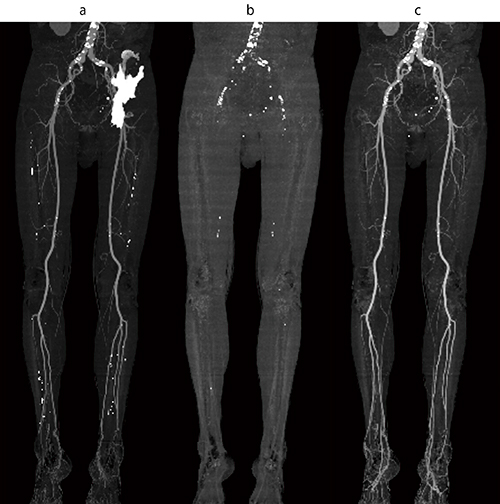

下肢3D-CTAにおいて,自動抽出では骨と接する骨盤領域の血管の抽出に失敗する場合がある(図4 a)。このような場合には,単純画像と造影画像をDual Maskで起動し,位置合わせをした後,単純画像で骨のみを除去したマスク(図4 b)を造影画像にコピーすることで,簡単に血管のみのVR画像・MIP画像が作成できる(図4 c)。

図4 マスクコピーを使った骨除去

a:造影CTから自動骨除去を行ったMIP画像

b:単純CTから骨除去したマスクMIP画像

c:マスク画像からマスクコピーした造影CTの基準MIP画像